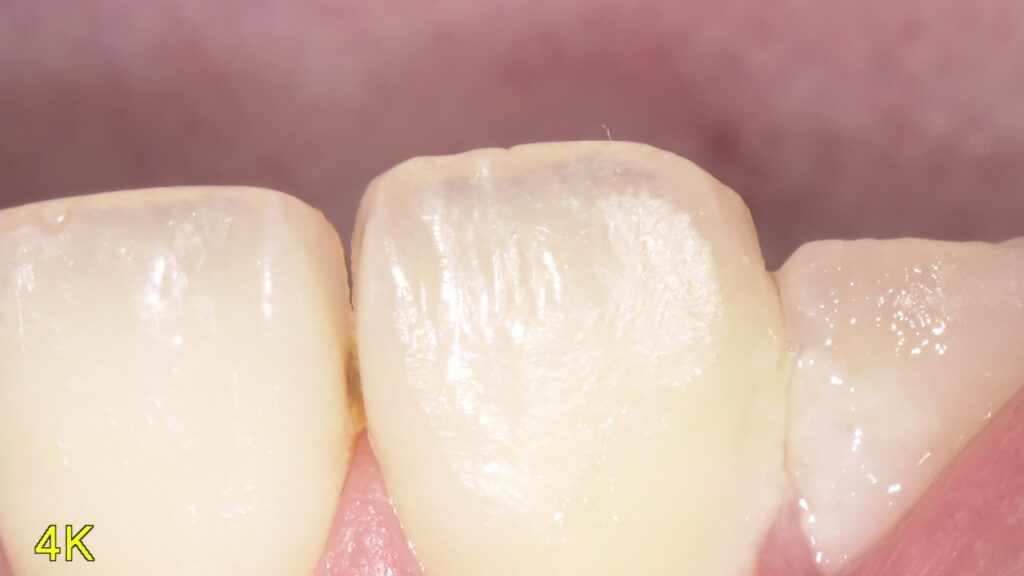

虫歯って患者さん本人には見えない位置にあったりしてなかなわかりにくいですよね

そのために当院では口腔内カメラを内蔵したマイクロスコープを使用して口腔内を説明しています。

写真を撮ったり、動画を撮ったりいろいろ使えるので重宝しています。

今回の写真は普段見えない位置の虫歯を撮影してみました。まだ小さいので症状はなにもないですが放置していたら広がってかけたり痛みが出てくると考えられるのでその前にしっかりと治していくのが大事です。

どんだけお話しするより現物を見てもらったほうがイメージわきますしどうなってるかわかるのでやはり動画や写真は大事なんだなと痛感しています。